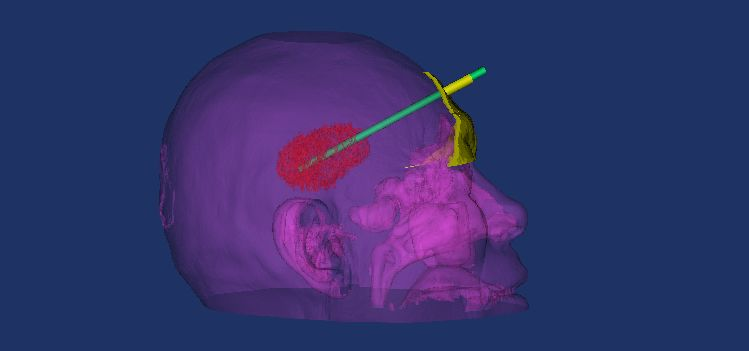

模拟引流管在导板引导下穿刺血肿

重建脑组织并透视化显示引流管穿刺血肿

引流管与血肿、面部的导板关系

待打印出的模拟穿刺导板、引流管及血肿